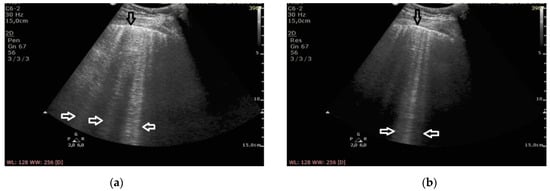

At the frequency of 6 MHz, cineloops recorded for patients with ILD presented Z-lines in 62% of the evaluated points and B-lines in 13%, whereas in 10% of the examined points the findings were mixed (Figure 1).

In patients with cardiogenic pulmonary edema, at the frequency of 6 MHz, B-line artifacts were present in 62% of the evaluated points, and Z-lines in 24%, including the mixed profile of B and Z in 16% of the examined areas (Figure 2). Consequently, the change in frequency leads to a change in the profile of vertical artifacts, whereas this phenomenon is much more frequent in patients with pulmonary fibrosis secondary to ILD. Collected data are demonstrated in Table 2.

The change of the ultrasound frequency from 2 to 6 MHz leads to a shortening or even the disappearance of vertical artifacts (conversion to A lines was observed in three cases), and this phenomenon is more characteristic for pulmonary fibrosis than edema (61% vs. 24% of the examined areas, p < 10−6).

Figure 1. Pulmonary fibrosis; (a) B-lines at 2 MHz (white arrows), irregular pleural line (black arrow), (b) Z-lines at 6 MHz (white arrows), irregular pleural line (black arrow).

Figure 2. Cardiogenic pulmonary edema; (a) B-lines at 2 MHz (white arrows), regular pleural line (black arrow), (b) B-lines at 6 MHz (white arrow), regular pleural line (black arrow).